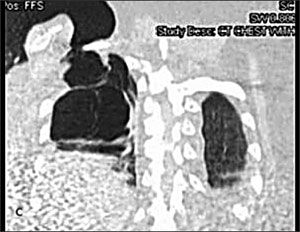

A chest radiograph showed herniation of a large right lung bulla through the intercostal space into the chest wall (A). This was confirmed on a CT scan of the thorax (B) with coronal reconstruction (C). His left lung was normal.

The herniation presents as a chest wall mass that may be asymptomatic or associated with pain or dyspnea. The mass is noncrepitant, which distinguishes it from subcutaneous emphysema and herniated lung parenchyma. Its dimensions change with the respiratory cycle: increasing with inspiration and decreasing with expiration. The hernia is usually easily reducible.

The diagnosis is readily made by imaging. CT provides additional information about the state of the underlying lung and orifice of the hernia.